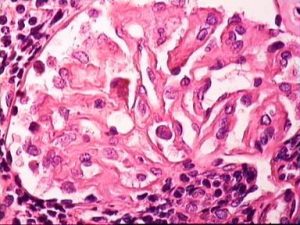

Sinh thiết thận: tiêu chuẩn vàng để chẩn đoán

• Tăng sinh lan tỏa tế bào nội mô và giãn mạch

• Xâm nhiễm bạch cầu đa nhân, bạch cầu mono trong bó mao mạch

• Có lắng đọng hình gò dưới biểu mô, dưới nội mô và trong khoang gian mạch cầu thận.

sinh thiết thận